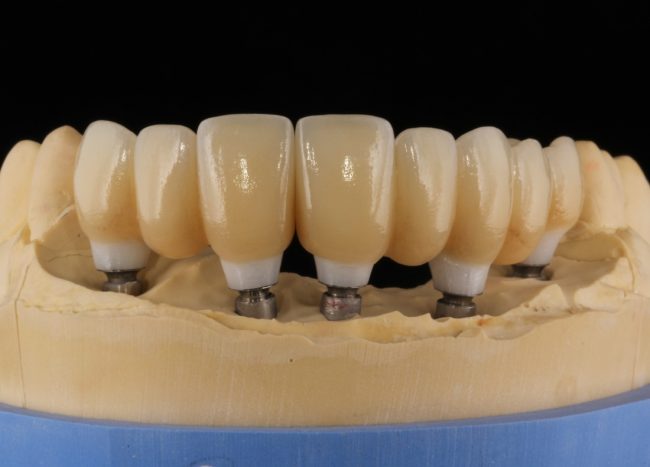

Рекомендации по установке имплантов. Для всех. Часть V.